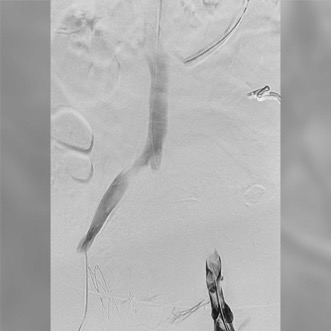

The focus was shifted to the left leg. A 0.035-inch guidewire was snared for through-and-through up-and-over access. The same Lightning Flash 3.0 was reintroduced and advanced across the iliocaval confluence. Thrombectomy of the left iliac system was successful. The through-and-through wire was removed such that left vein thrombectomy could be performed as well. After three passes, a significant amount of thrombus was removed. Final angiography demonstrated restored patency after placement of an Abre™ stent (Medtronic).

Angiogram of left iliac Angiogram of left iliac

Pre—Angiogram of the left iliac system shows significant thrombus.